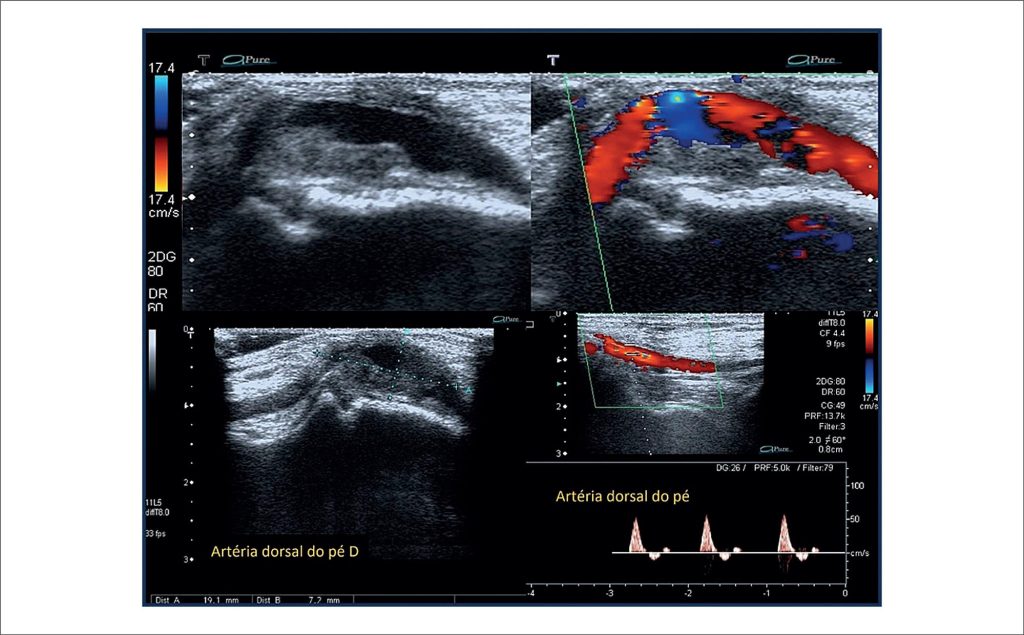

Aneurisma da Artéria Dorsal do Pé: Diagnóstico Ultrassonográfico

O aneurisma da artéria dorsal do pé (artéria pediosa) foi descrito pela primeira vez em 1907. Desde então, outros autores relataram esse raro tipo de aneurisma, porém suas manifestações clínicas ainda são pouco conhecidas. Com apenas 24 casos relatados na literatura até 2017, segundo Aragão et al., o aneurisma da ADP é mais comum em homens (63%) com média de idade de 55,4%. Em geral, apresenta-se como uma massa pulsátil, podendo evoluir com microembolização, hemorragia, ruptura e compressão nervosa. O exame físico geralmente apresenta uma massa pulsátil que pode causar dor, parestesia e desconforto ao caminhar ou usar calçados, queixas semelhantes às do caso aqui relatado.